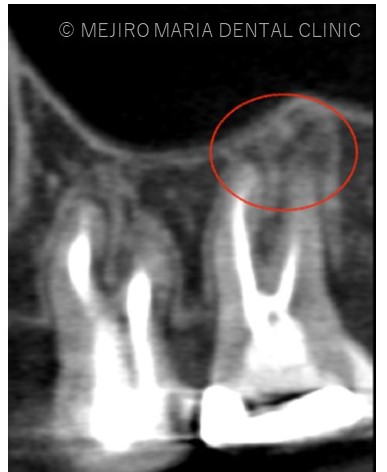

また、同時に近心根には見逃している根管もしくはフィンと言われる極小なスペース(CT画像2赤丸)が存在することも確認できます。

治療中に歯科用顕微鏡(マイクロスコープ)下にてCT画像で確認した部位には手つかずの根管を確認し、処置を行った。

また、今回はCT画像上で手つかずの根管を確認できましたが、上顎臼歯部(上の奥歯)はMB2という解剖学的に発見が難しい根管が約90%の確率で存在し、その形態は様々です。歯科用顕微鏡(マイクロスコープ)が開発される前までMB2の発見率は約60%という報告が主でした。つまり、この30%の発見率の上昇が顕微鏡(マイクロスコープ)による根管治療の精度だとも考えられます。

しかしながら、MB2は歯質の薄いところに存在するため場所を見誤ると偶発的に穿孔を起こしやすく、無駄な歯質を削合し歯の寿命を縮める原因となることもあります。マイクロスコープの一つひとつの手技は適切なトレーニングと歯牙の解剖学的な形態の熟知が必要になります。